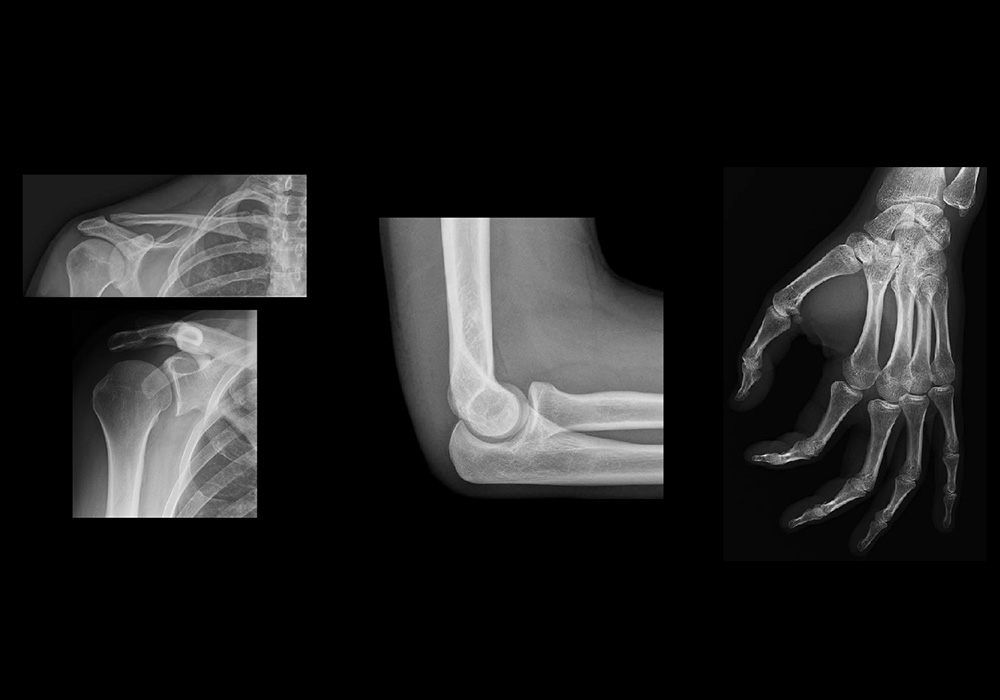

Contamos con un equipo de profesionales con amplia experiencia en áreas de Radiología

Convencional, Radiología de Emergencia para Traumatología, Procedimientos Especiales con

medios de contraste y Radiología Pediátrica.

ESTUDIOS ESPECIALES

Requisito para estudios de Rayos X

INDICACIONES PREVIAS